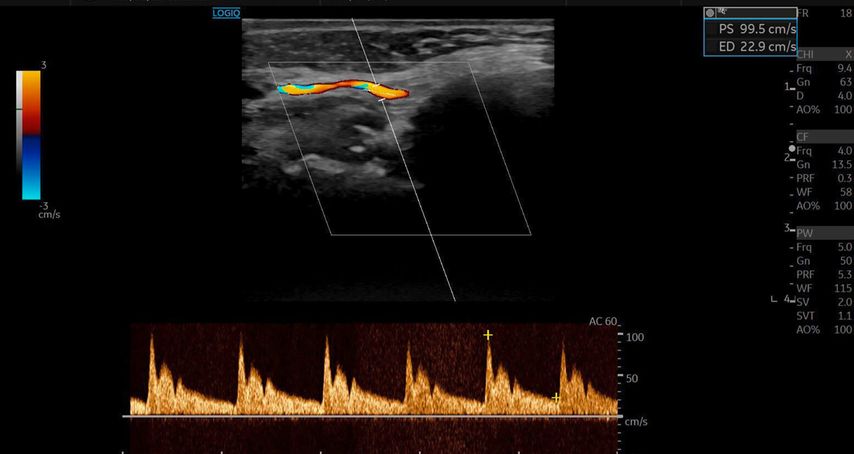

Die Duplexsonografie ergab folgende Befunde (Abb. 5 und Abb. 6):

-

Der Durchmesser der A. angularis und A. facialis hatte sich nahezu verdoppelt.

Die systolische Spitzengeschwindigkeit (PSV) stieg von 20cm/s auf über 100cm/s.

Die enddiastolische Geschwindigkeit (EDV) betrug nun 20cm/s, was auf eine periphere Vasodilatation und eine Wiederherstellung der Makrozirkulation hindeutete (Abb. 7).